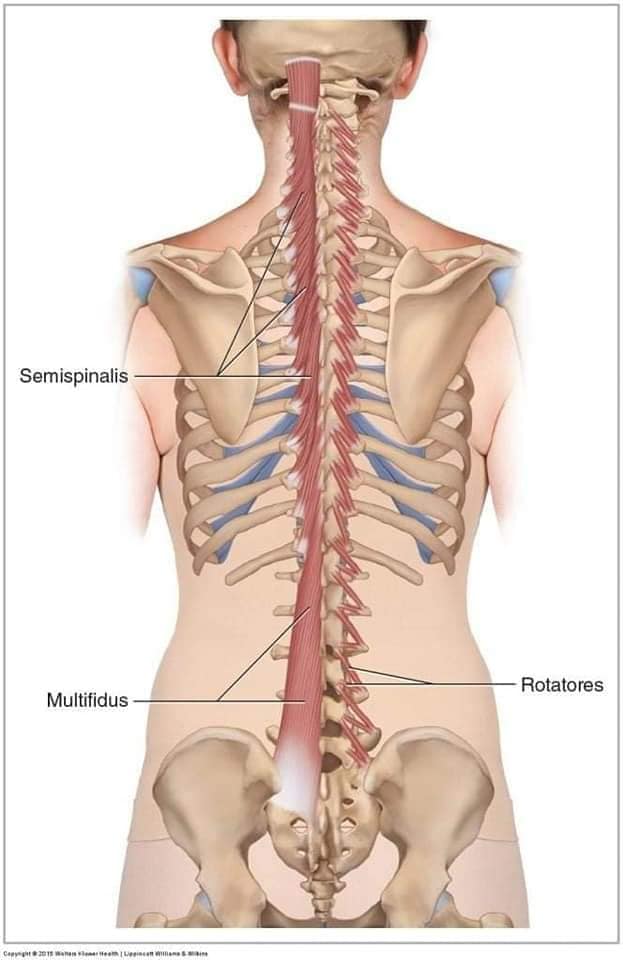

Глибинні спинні м'язи

М'язи, що забезпечують стабільність хребта: М'язи, що розташовані між хребцями: включають мускулатуру, яка забезпечує стабільність і підтримку хребта, а також дозволяє здійснювати рухи хребта.

М'язи, що здійснюють ротацію та нахили

М'язи, що забезпечують ротацію хребта: Ротаційні м'язи: допомагають у здійсненні обертальних рухів тулуба, а також у підтримці рівноваги і стабільності хребта.